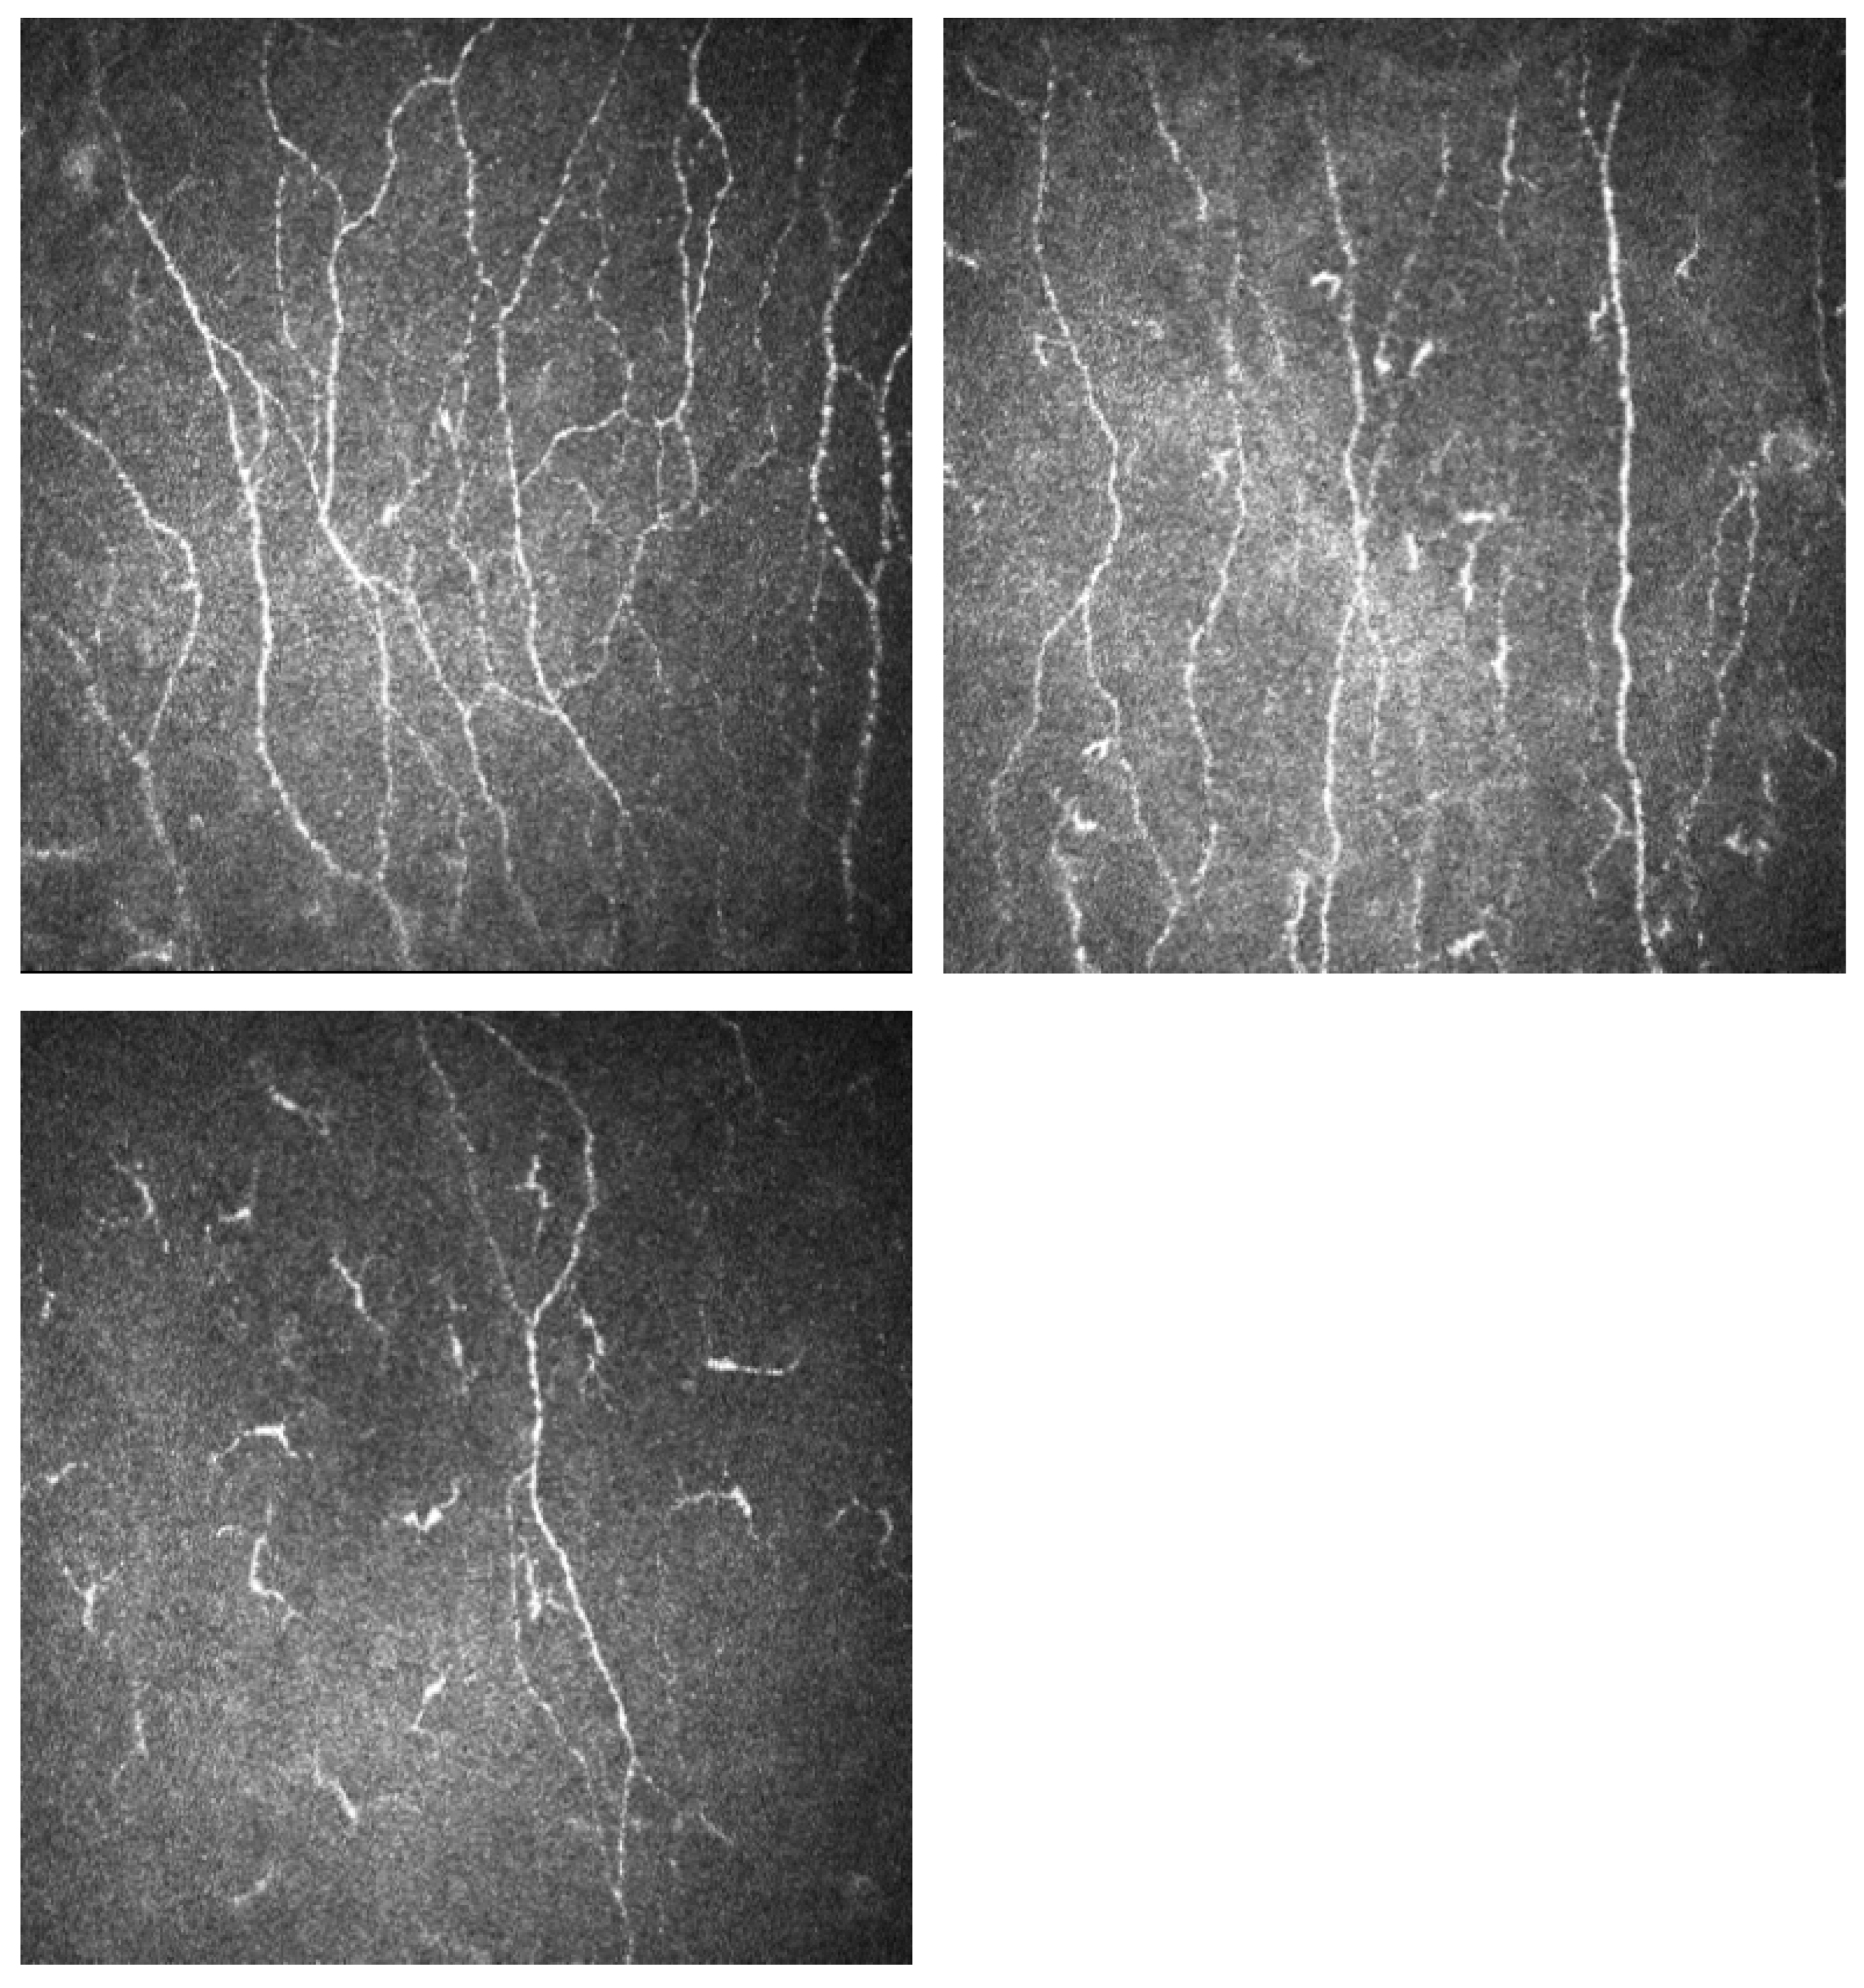

2.5. Corneal Confocal Microscopy

| CNFL (mm/mm2) | 21.08 (2.77) | 20.35 (2.46) | 9.78 (4.58) | 5.17 (1.82) | <0.001 | <0.001 | <0.001 |

| CNFD (no./mm2) | 25.02 (4.27) | 23.06 (6.21) | 11.50 (5.08) | 6.00 (2.59) | <0.001 | <0.001 | <0.001 |

| CNBD (no./mm2) | 26.94 (7.28) | 21.53 (7.27) | 11.51 (6.84) | 5.71 (3.43) | <0.001 | <0.001 | <0.001 |